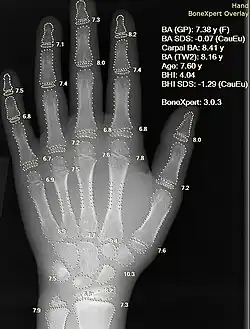

Künstliche Intelligenz wird mittlerweile auch eingesetzt, um beispielsweise genetisch bedingte und seltene Knochenerkrankungen schneller zu erkennen.[35] Dabei wird die KI auf charakteristische Bildmuster verschiedener Skelettdysplasien trainiert. Durch die vielfältige Ausprägung verschiedener Muster im Skelett, die in der Diagnose identifiziert werden müssen, ist es selbst für erfahrene Kliniker schwer, eine eindeutige Diagnose auszusprechen, so dass es dadurch oft zu einer langen Wartezeit von mehreren Jahren für Patienten sowie zu Fehldiagnosen kommt.